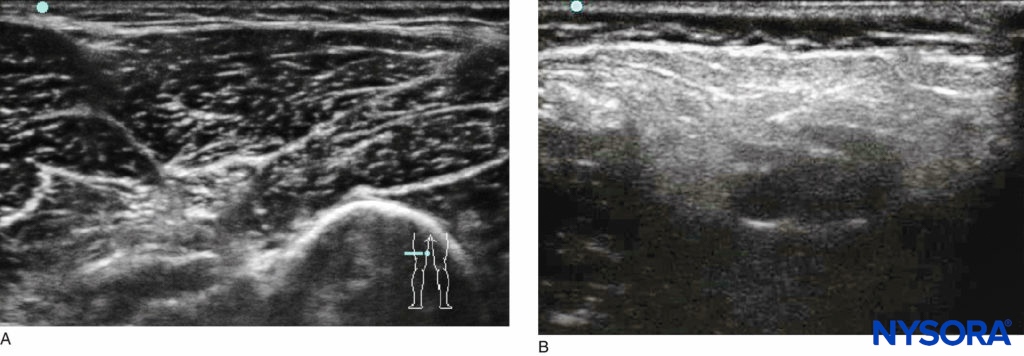

US-guided regional anesthesia has been with us for more than a decade; interest in this technology to aid in nerve localization has significantly increased, coinciding with increasing world-wide experience and the advances made in portable US equipment. US has been shown to reliably identify nerves and fascial planes in children, plan the safest needle trajectory, and visualize the dispersion of local anesthetic within the desired tissue planes. This technology, however, requires significant training and skill for its successful implementation; the success of US techniques is highly operator dependent. The key to the successful use of US is a specific training module and mentorship from a skilled practitioner. Although children are generally easier subjects to scan due to the superficial nature of their nerves, there are challenging morbidities (eg, cerebral palsy; Figure 1).

FIGURE 1. Comparison of US images of the popliteal fossae in (A) a healthy child and (B) a child with cerebral palsy.

To succeed with these difficult patients, the operator must have an established routine for each block, such that similar scan-ning conditions are used each time so that the expected US pattern is easily recognized.